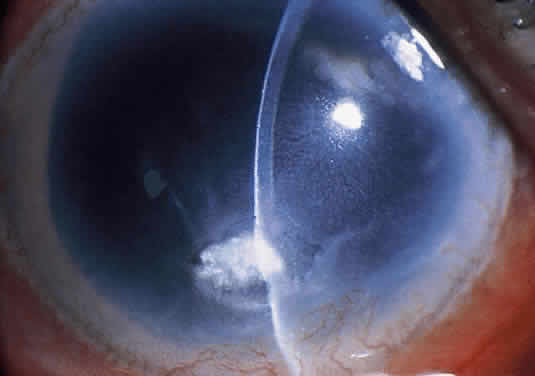

Corneal ulcers caused by S. pneumoniae are typically described as serpiginous or creeping and most often spread toward the center of the cornea. They are characterized by a gray-yellow disc-shaped ulcer with an overhanging margin at the advancing edge (Fig. 5). The ulcer usually progresses rapidly, extending into the deep stroma and often leading to corneal perforation. Extensive damage to corneal tissue, as well as a characteristic sterile hypopyon, are caused by the rapid production of bacterial exotoxin within the stroma.40,41